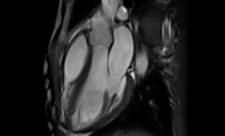

סורקי ה-MRI, המשמשים ככלי אבחון ומחקר, קיימים בעולמנו כבר כארבעה עשורים, מאז התקנתו והפעלתו של סורק ה-MRI הראשון ...

סורקי ה-MRI, המשמשים ככלי אבחון ומחקר,...